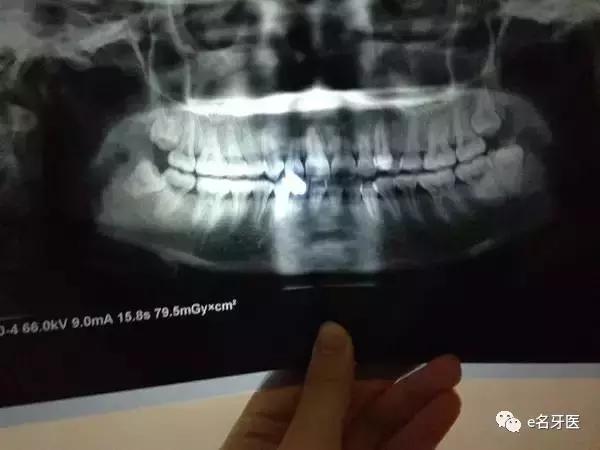

▲这就是牙齿模型,一点都不恐怖对不对

医生的治疗建议是:

上下各拔一颗,调整好牙中线和*牙虎**的位置。